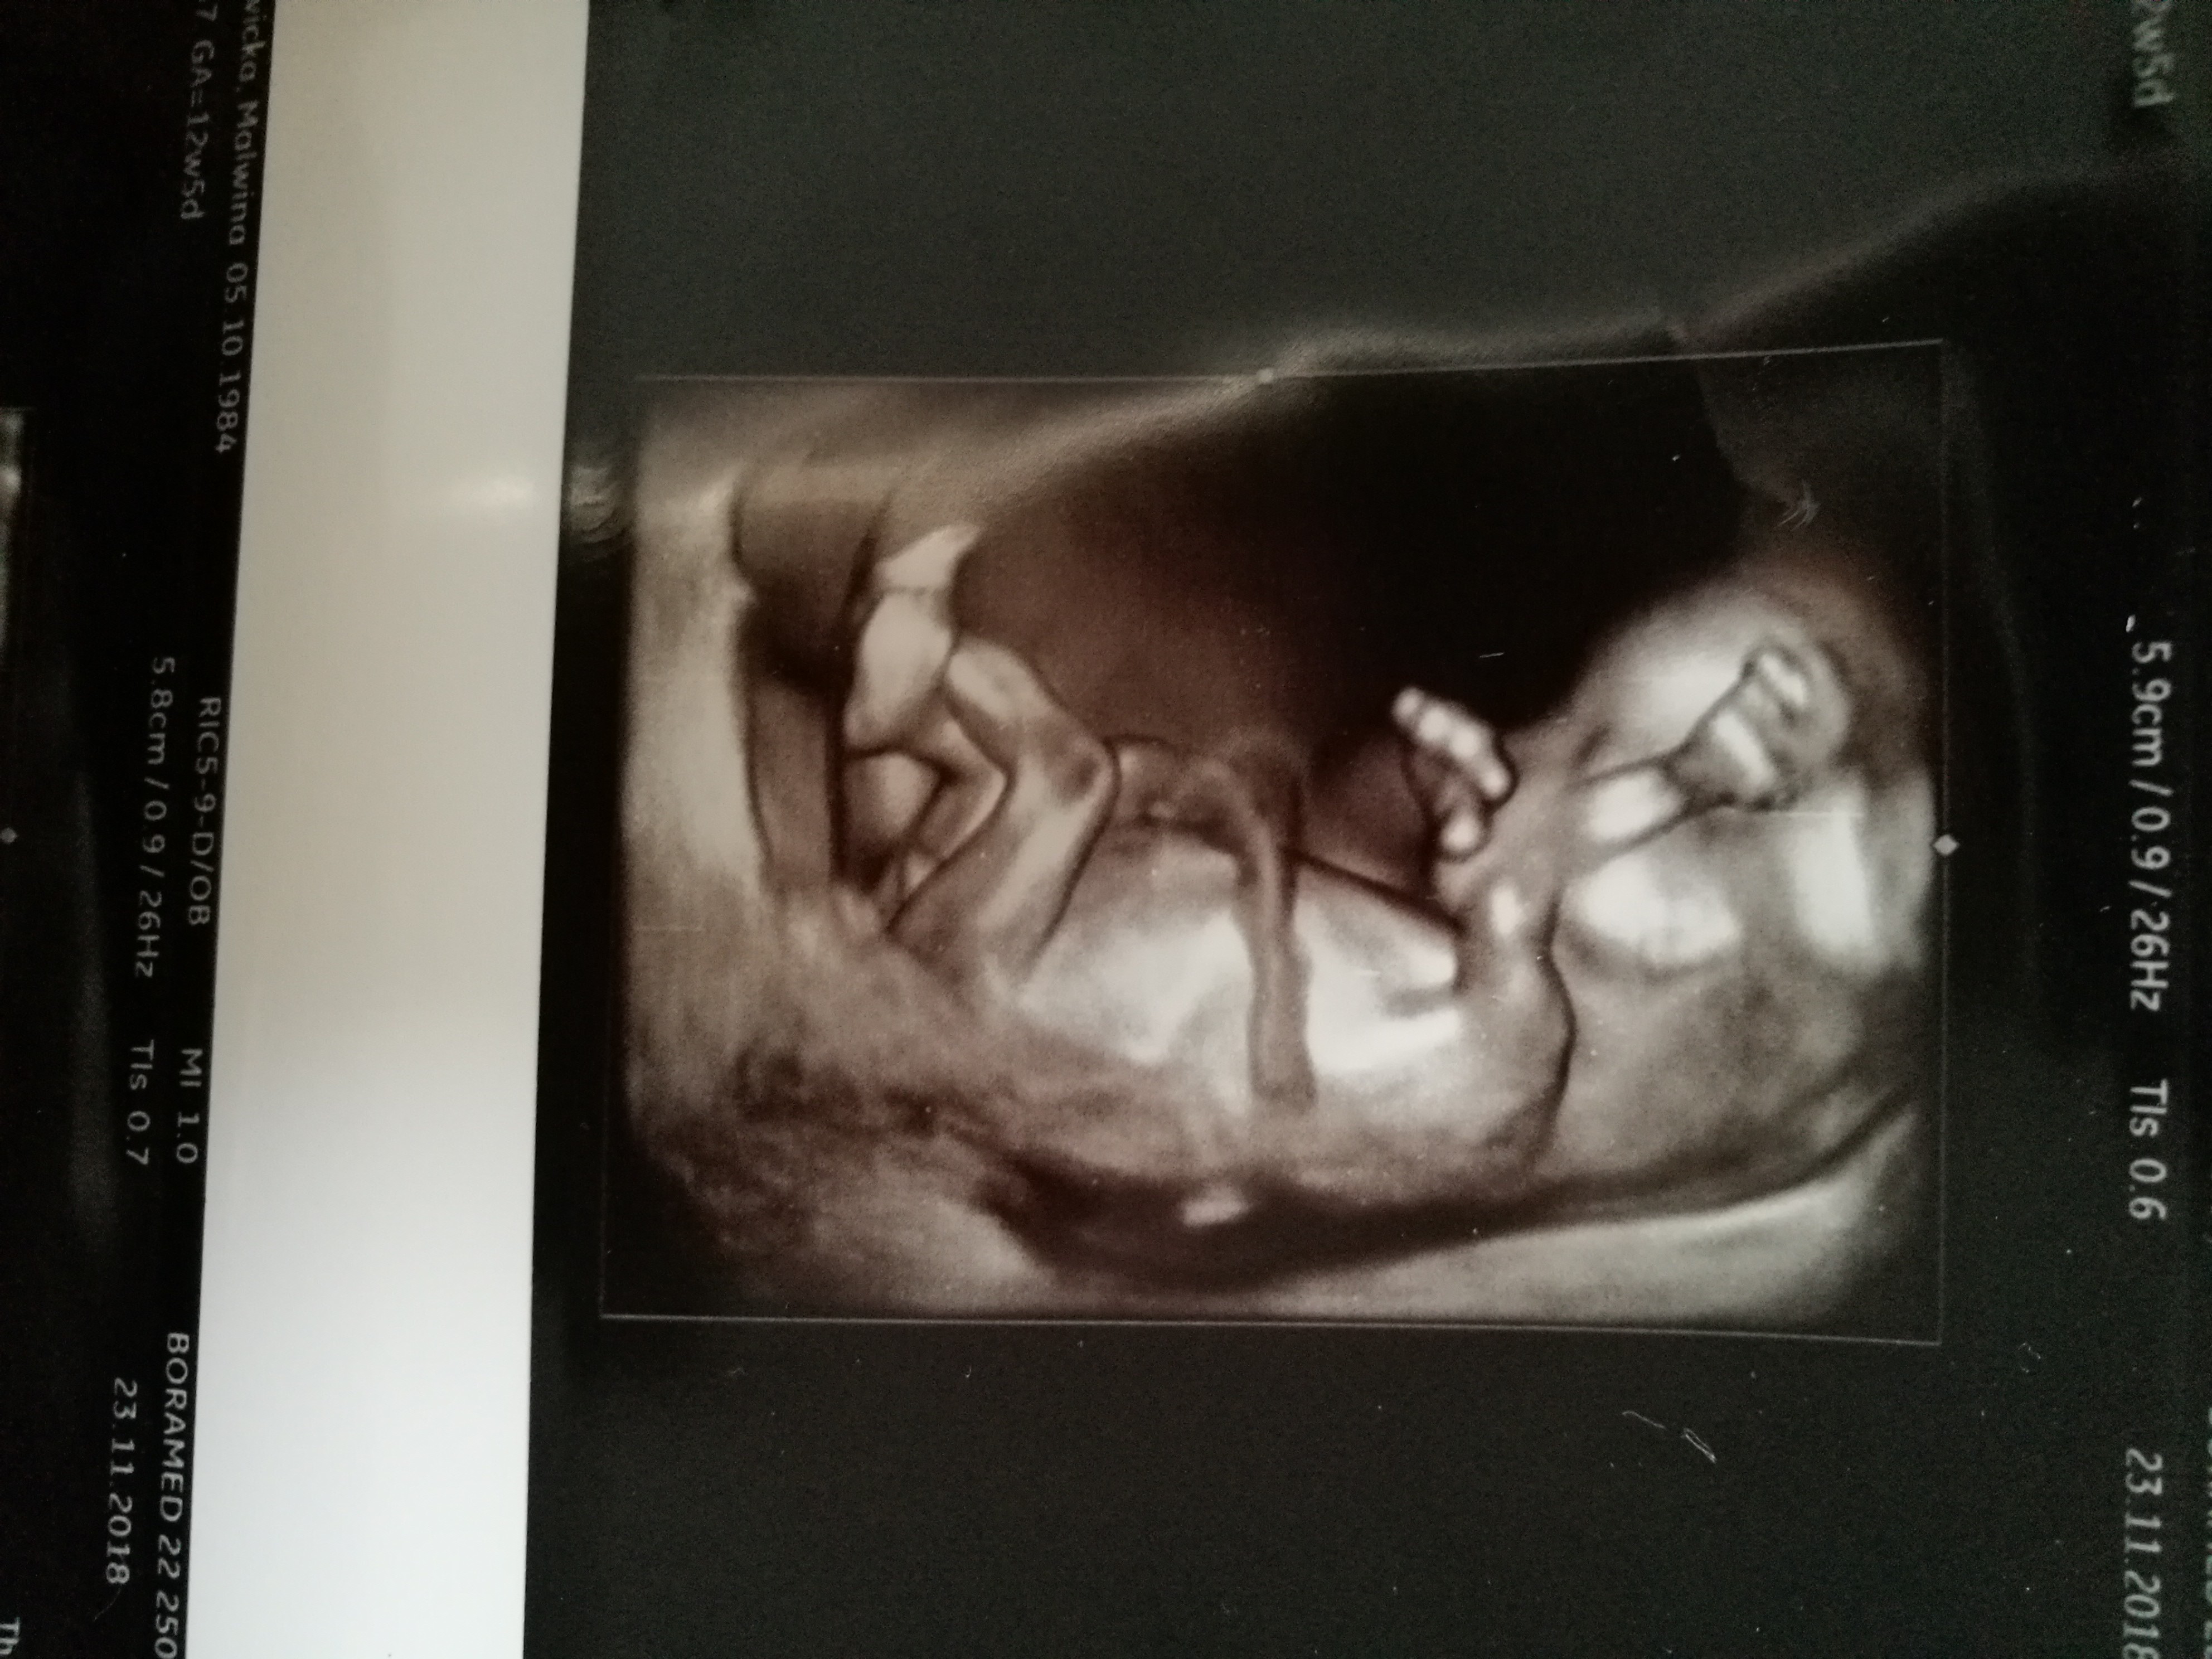

Witam w 19 tygodniu ciąży dowiedziałam się ze będę miała dziewczynkę w 20 tyg okazało się jednak , że to chłopak. Sama już nie wiem bo na jednym usg widać na pewno dziewuche a na drugim chłopca. Może to pempowina ?? Może ktoś mi pomoże rozwiązać ta zagadkę

Cześć dziewczyny. Co sądzicie o moich zdjęciach? W 11tc5dc pierwsze zdj-lekarz stwierdził że na 75prc. dziewczynka. Tydzien później jeszcze raz byłam u niego, bo jeszcze musiał coś podejrzeć i w 12tc5d następne zdjęcia-powiedział że dziś na 75 prc. chłopak. Powiedział ogólnie że daje 50proc i trzeba poczekać do połówkowego. Czy ktoś miał tak szybką zmianę płci. Zdjęcia z obydwu badań wydają się jednoznaczne: na pierwszym dziewczynka, na drugim chłopiec. Czy już zostanie chłopiec?? Czy jest szansa że się zmieni? Ktoś tak miał? Dałybyście 100proc chłopak, czy jakąś nadzieję na dziewczynkę? Lekarz uznał, że jest jakiś procent kobiet u których się to zmienia, nie wiem co miał na myśli.